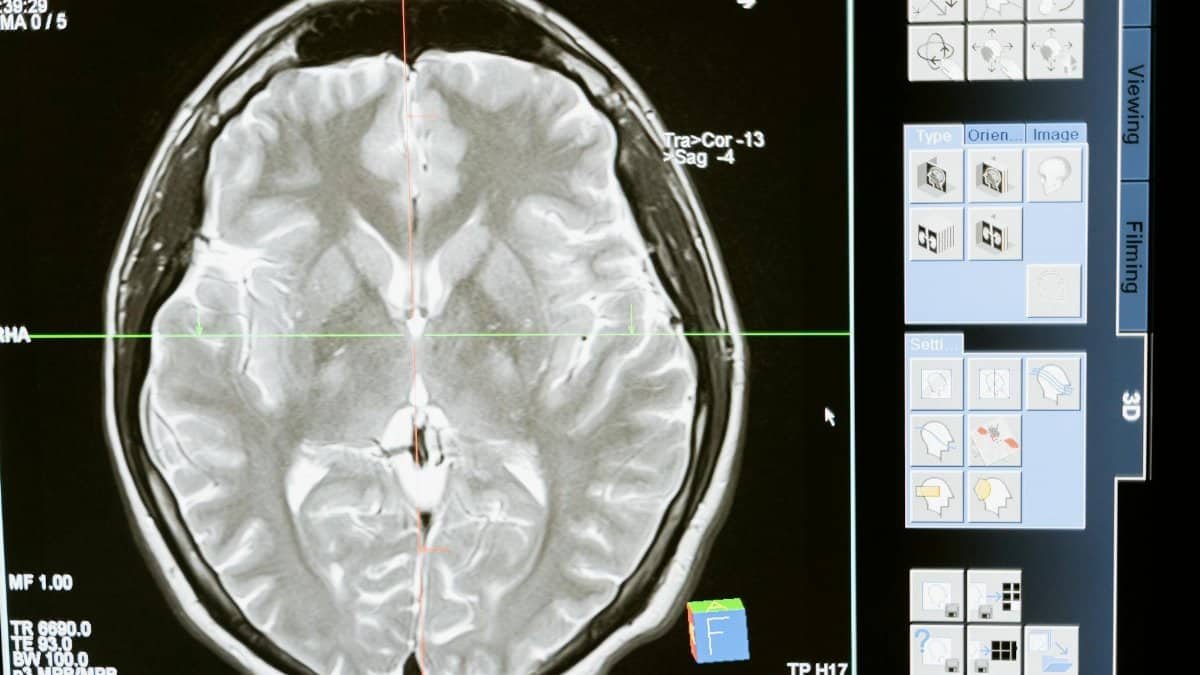

Bluetooth headphones sit uniquely close to sensitive tissues. Positioned directly inside the ear canal, they emit radiation mere millimeters from neural pathways. This placement maximizes exposure compared to other wearables, like smartwatches on the wrist. Scientists emphasize how this intimacy sets earbuds apart, fueling their alarm over cumulative effects. U.S. users, embracing cord-free audio, may overlook this proximity in their rush for convenience.

Bluetooth radiation refers to the radiofrequency electromagnetic fields generated by these wireless connections. Operating at low power levels, the signals enable short-range data transfer but raise flags when sustained near the head. The scientists’ concerns stem from this nonstop emission inside the ear canal, where absorption could differ from distant sources. For context, similar radiofrequency queries have prompted reviews by federal agencies, as detailed on the FDA’s page on wireless device safety.

Ear canal devices place Bluetooth radiation perilously near the brain. Scientists highlight this as the crux of their warning, noting how signals penetrate soft tissues en route to auditory processing centers. All-day wear intensifies the scenario, potentially altering risk profiles versus held-away phones. The 2026 alert positions this as a headphone user flashpoint, urging vigilance in a tech-saturated U.S. landscape.